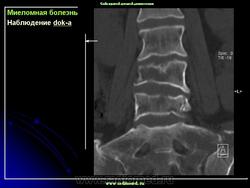

Множественная миелома позвоночника

Миеломная болезнь